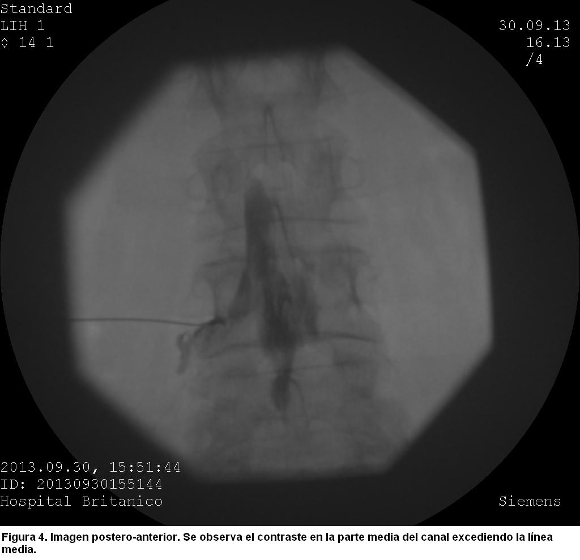

Esta imagen se acompañó en la visión postero-anterior, de una densa colección de medio de contraste confinada a la porción central del canal espinal, que excedía la línea media (figura 4).